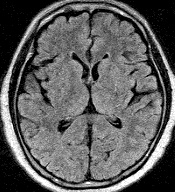

左の写真は正常な人の頭部MRI写真の1コマを3種類見本に貼り付けたもので、私の脳みその写真ではありません。

私は、本やテレビでよく見る、この正常な人の写真を頭に描きながら目の前にある自分の写真を詳細に観察しました。私の脳みそは、元気でした。頭蓋骨の中が狭すぎると言わんばかりにぎっしりと詰まっていました。